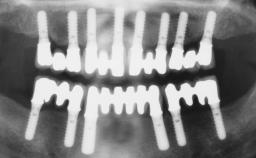

Rehabilitating an Edentulous Maxilla with a Fixed Dental Prosthesis Following Provisional Immediate Loading

This case features the flapless computer-guided placement of 7 bone-level implants, distributed to provide maximal support for the prosthetic framework. A rigid one-piece metallic framework was utilized as an interim restoration to reduce the risk of fracture associated with this prosthetic design. As part of the clinical examination, the SAC Assessment Tool was used, resulting in a surgical and restorative risk classification as “complex”.

# of Implants 7

Type of Implants Two-Piece

Guided Surgery Yes

Prosthesis Type FDP

SAC Level Complex

Defining Characteristics Fully edentulous upper jaw to be rehabilitated with four or more implants

Modality 6+ implants with immediate loading

Defining Characteristics Fully edentulous upper jaw to be rehabilitated with an implant-borne fixed dental prosthesis

Loading Protocol Immediate